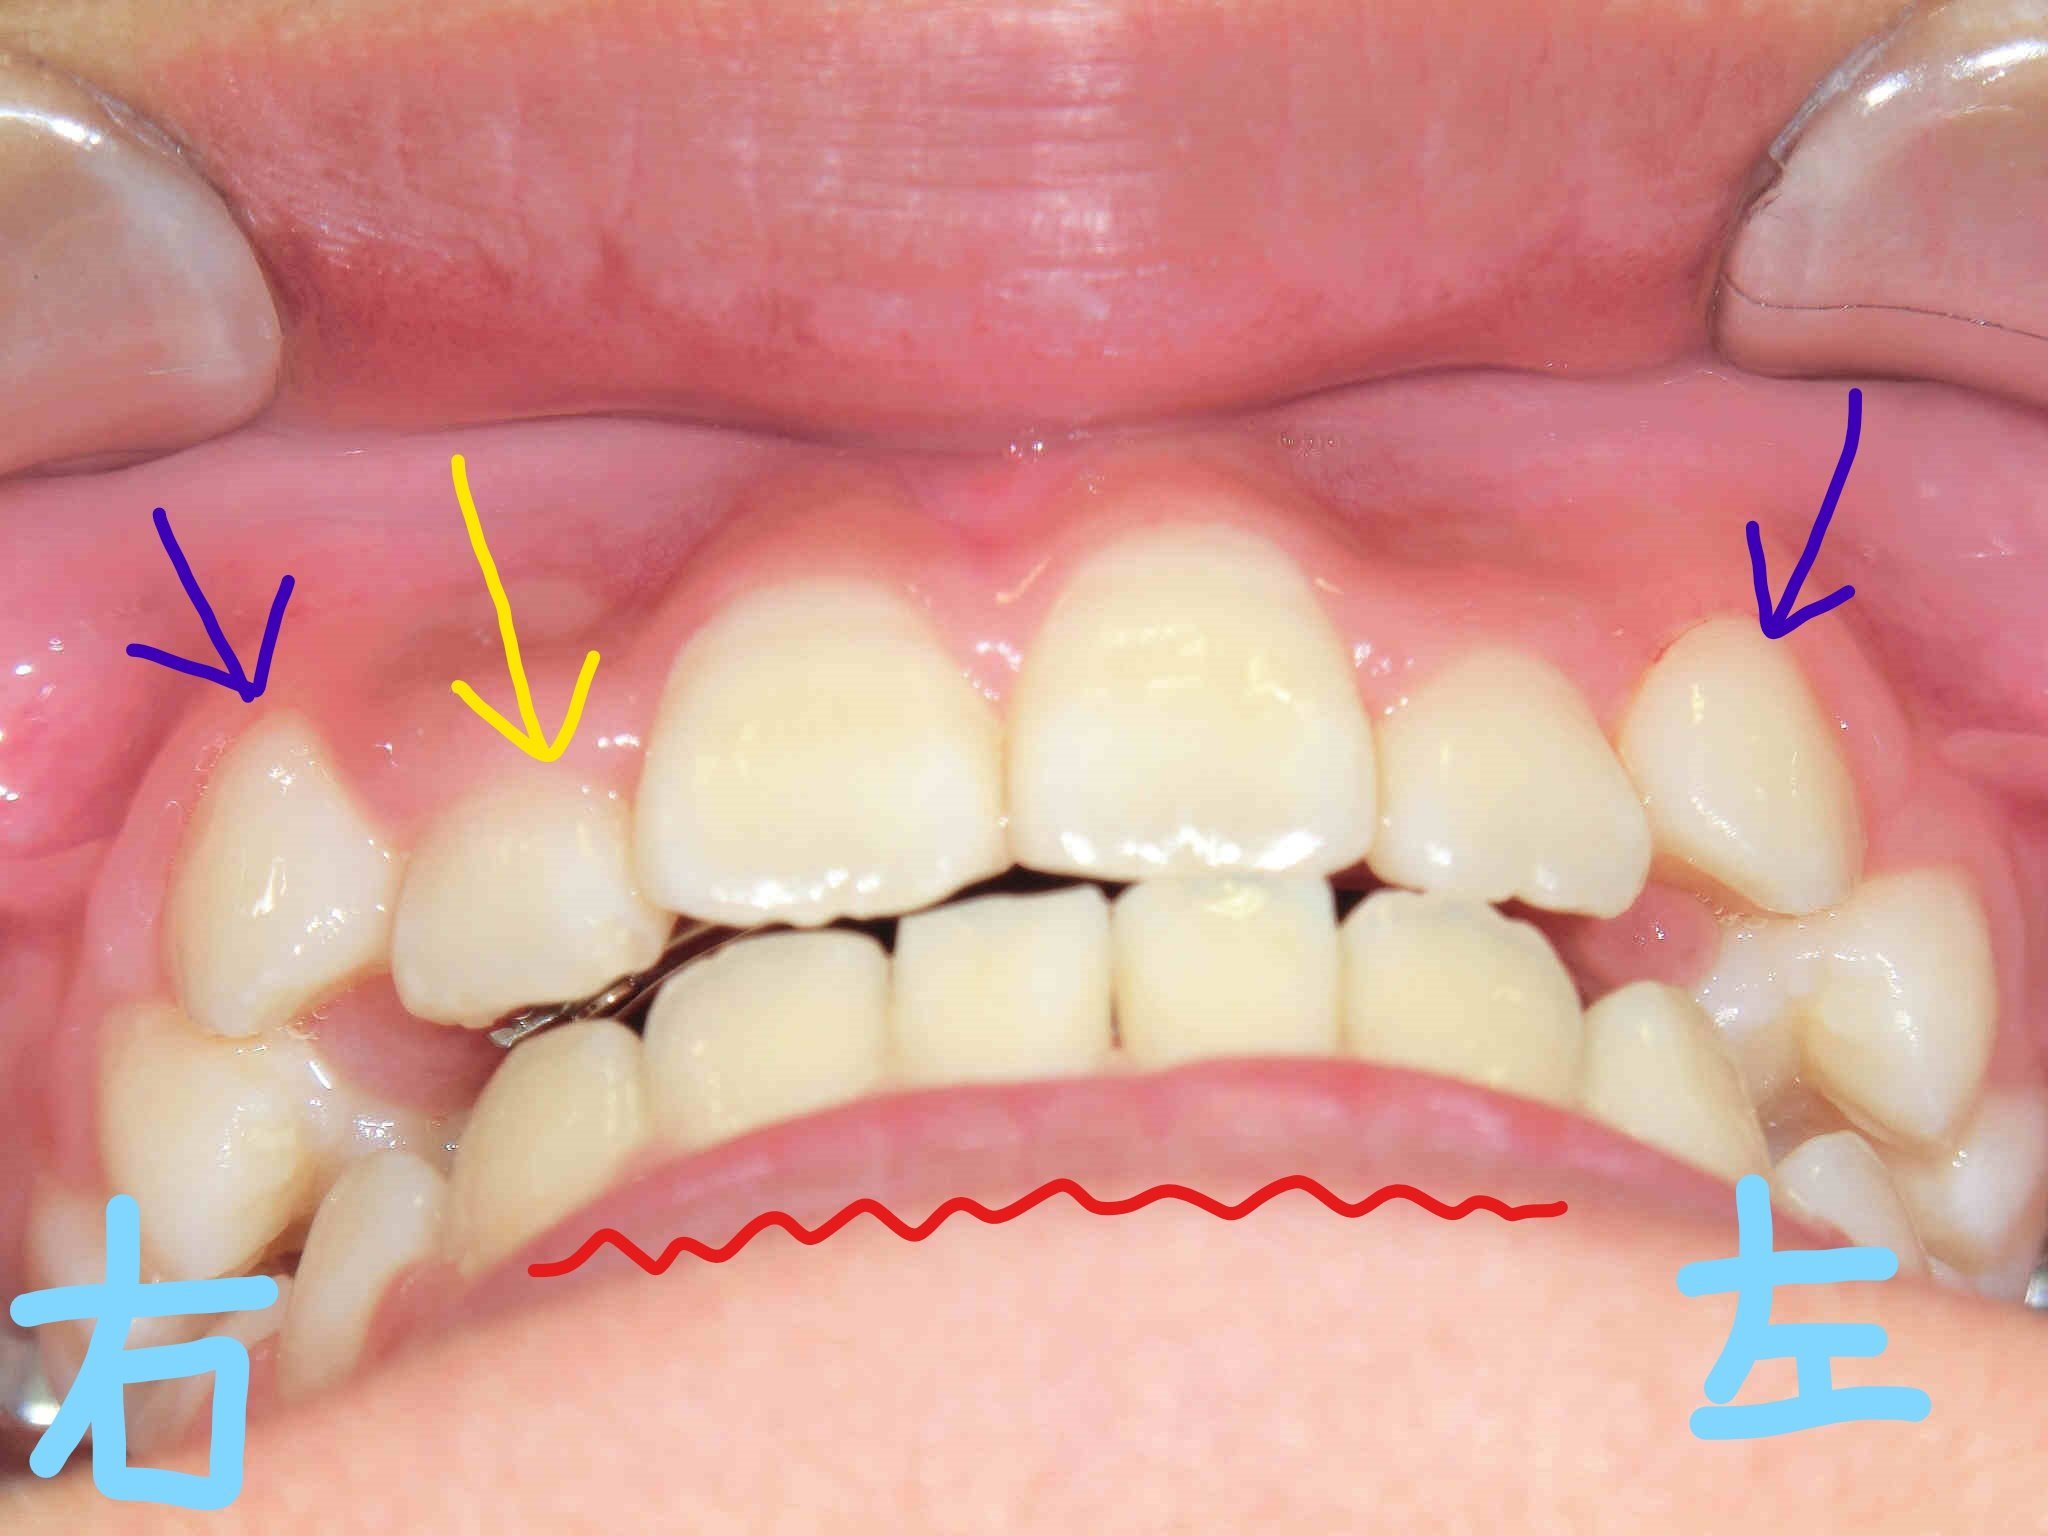

左上は正面からの口腔内写真、右上は下から見上げた正面の写真です。下顎前歯(赤色波線部)の叢生(いわゆるガタガタの歯並び)は改善が見られ、歯列が整ってきています。

一方で、上顎歯列の拡大により右上前歯(黄色矢印)は前方へ誘導され、良好な方向へ変化しつつありますが、両側の上顎犬歯(紫色矢印)が歯列の外側に位置しているため、歯列内に誘導するにはさらなるスペースの確保が必要と判断しました。そのため、上顎に固定式の拡大装置(急速拡大装置〈RPE〉)を使用する方針といたしました。